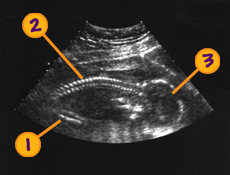

- Nú er góður tími til að fara í sónar. Þá er meðgöngulengdin metin, hvar fylgjan er staðsett, legvatnsmagnið er metið og hugsanlegir fósturgallar greindir.

- Nú er fóstrið orðið það stórt að auðveldara er að skoða einstök líffæri og líffærakerfi

- Meðgöngulengd er reiknuð út frá stærð höfuðsins og lengd lærleggjarins

Fjölburaþunganir greinast ef ekki hefur verið ómskoðað áður. - Staðsetning fylgju er skoðuð